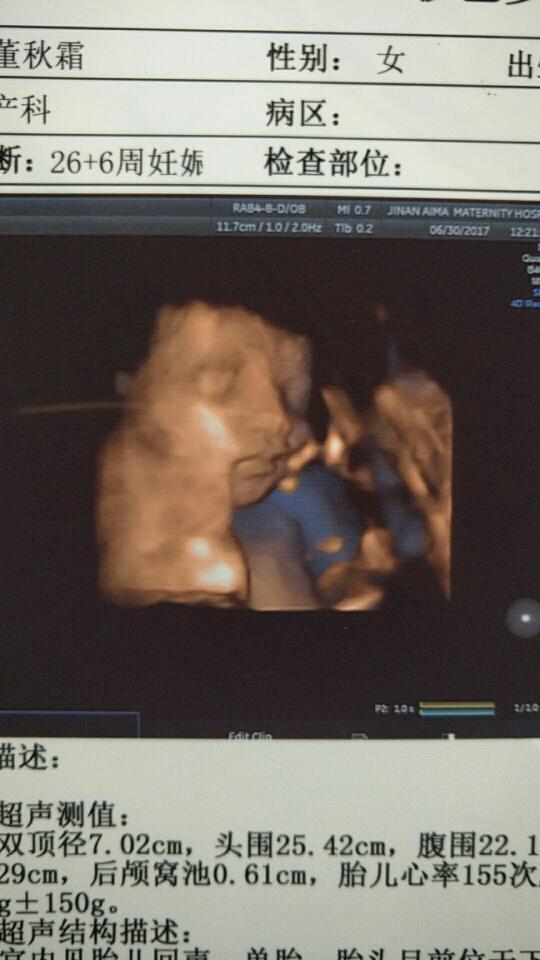

今天虽搁唉索然等了好长时间,但是四维一次通渐露过我家宝宝果真没让我失望,间梨第一次看见你的样子心里好开心虽然有点丑丑的,不知道是随你爸爸还是妈妈我。。。😝😝😝